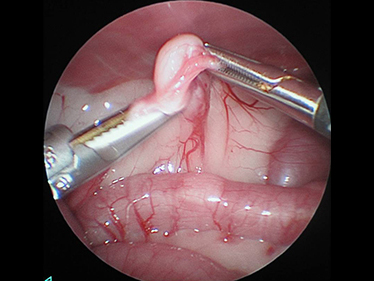

お腹に小さな穴を開けてとトロッカーを差込みます。

卵巣をつかみ超音波メスで切り取ります。

手術の傷も大変小さく、術後3時間でお水も飲んでいました。大変調子もよく、その日に退院しました。